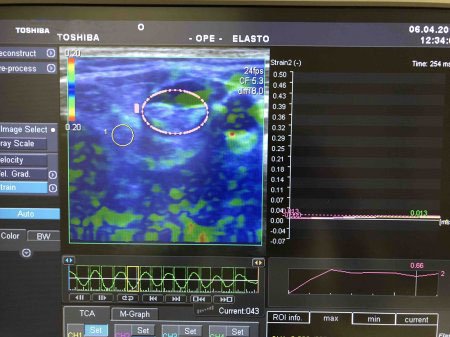

После компьютерной обработки изображение передается на экран монитора, по которому врач с высокой долей вероятности может интерпретировать результаты исследования.

Неоднородные элементы ткани сокращаются по-разному вследствие неодинаковой эластичности и отражаются на экране монитора различным цветом.

При исследовании используют 4-х точечную шкалу эластичности, демонстрирующую различную степень жесткости структур. В тканях 1 типа обнаруживают высокую эластичность; во 2 типе – среднюю эластичность; в 3 типе отмечают промежуточную эластичность; 4 типу соответствуют ткани с высокой жесткостью.